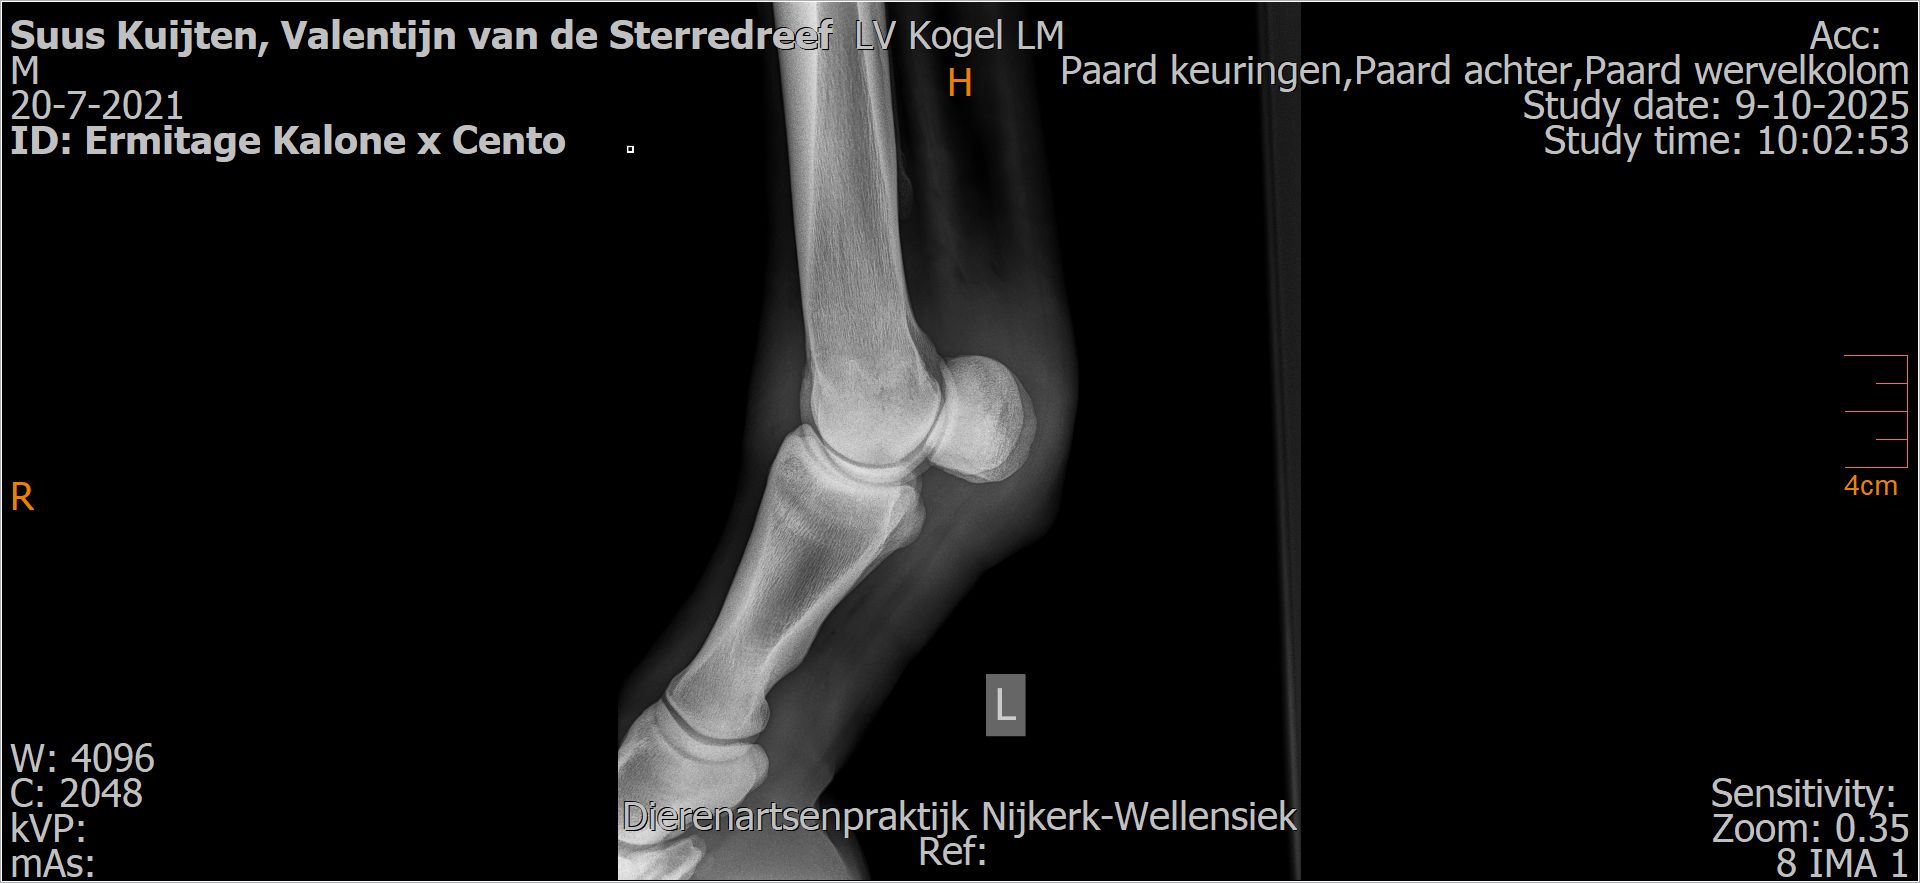

Valentijn van de Sterredreef

Leeftijd:

4

Röntgenfoto’s